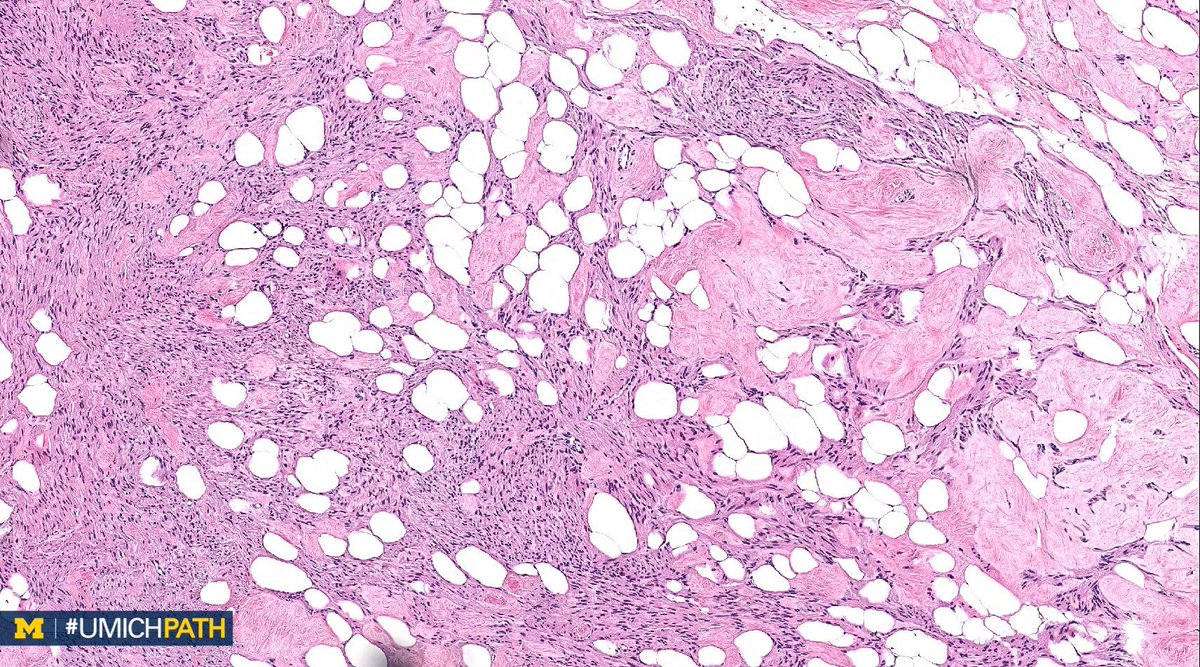

We're sharing 2 cases today since we missed #GYNPath Day 5 last week. What’s your #DailyDx of this uterine mass? We’ll tweet the answer and some quick facts tomorrow! #UMichPath

What’s your #DailyDx of this uterine mass?

We’ll tweet the answer and some quick facts tomorrow! #UMichPath

A: Lipoleiomyoma. A variant of uterine leiomyomata. Gross: Well circumscribed mass with alternating yellow and white areas. Histo: Variable admixture of bland smooth muscle cells and adipocytes. Very rarely can have glandular elements (adenolipoleiomyoma). #GYNPath #DailyDx

UMichPath's tweet image. A: Lipoleiomyoma. A variant of uterine leiomyomata.  Gross: Well circumscribed mass with alternating yellow and white areas. Histo: Variable admixture of bland smooth muscle cells and adipocytes. Very rarely can have glandular elements (adenolipoleiomyoma). #GYNPath #DailyDx